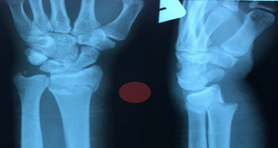

Often an extra-articular fracture, displaying a consistent displacement pattern, including dorsal angulation, shortening, radial deviation, and radial tilt. This is the so-called Colle’s fracture, and patients typically present with a ‘dinner fork’ deformity of the wrist. When the angulation is volar, it is called Smith’s fracture.

The radiographic criteria for an acceptable reduction of a distal radius fracture are:

- Radial length of more than 5mm.

- Radial inclination angle of more than 15o.

- Sagittal articular tilt of less than 7o dorsal tilt.